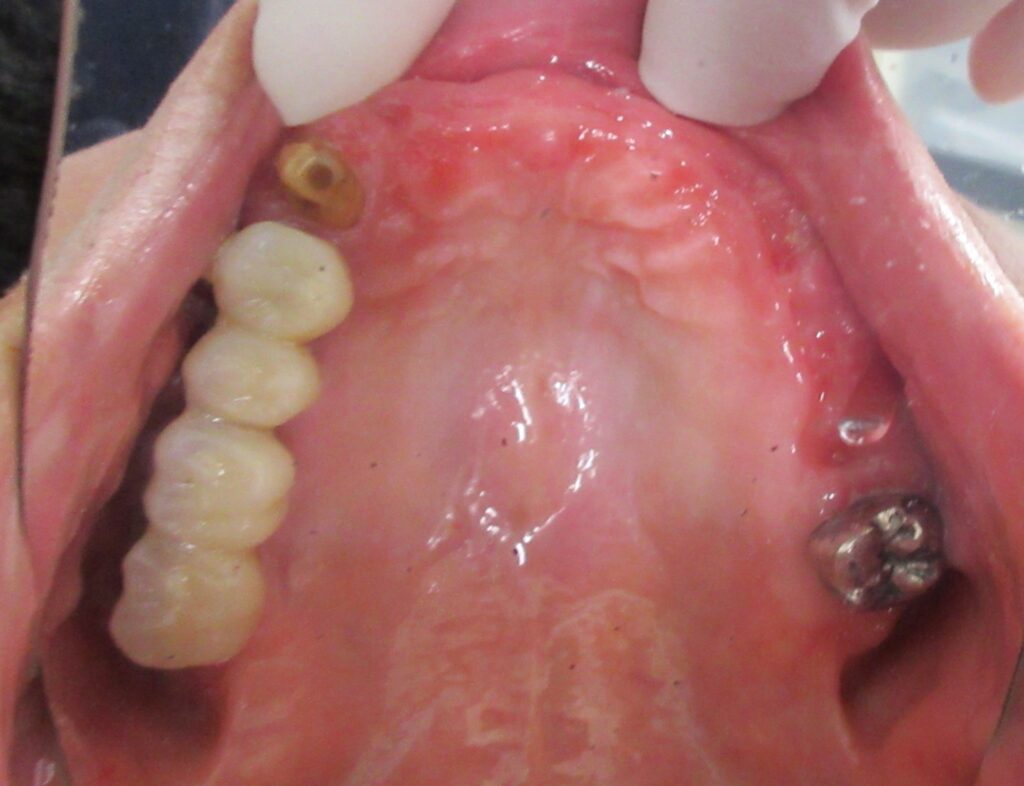

当日の様子は、まず診療室に入っていただき、簡単にお口の中の全体的なお掃除と麻酔、仮歯を外す処置、CGFのための採血を行います。

まずは右上1番目の歯茎から骨の部分までを穴開けパンチの要領で穴を開けていきます。

くりぬいた部分の歯肉を取り除き、次は骨に穴を開けていきます。